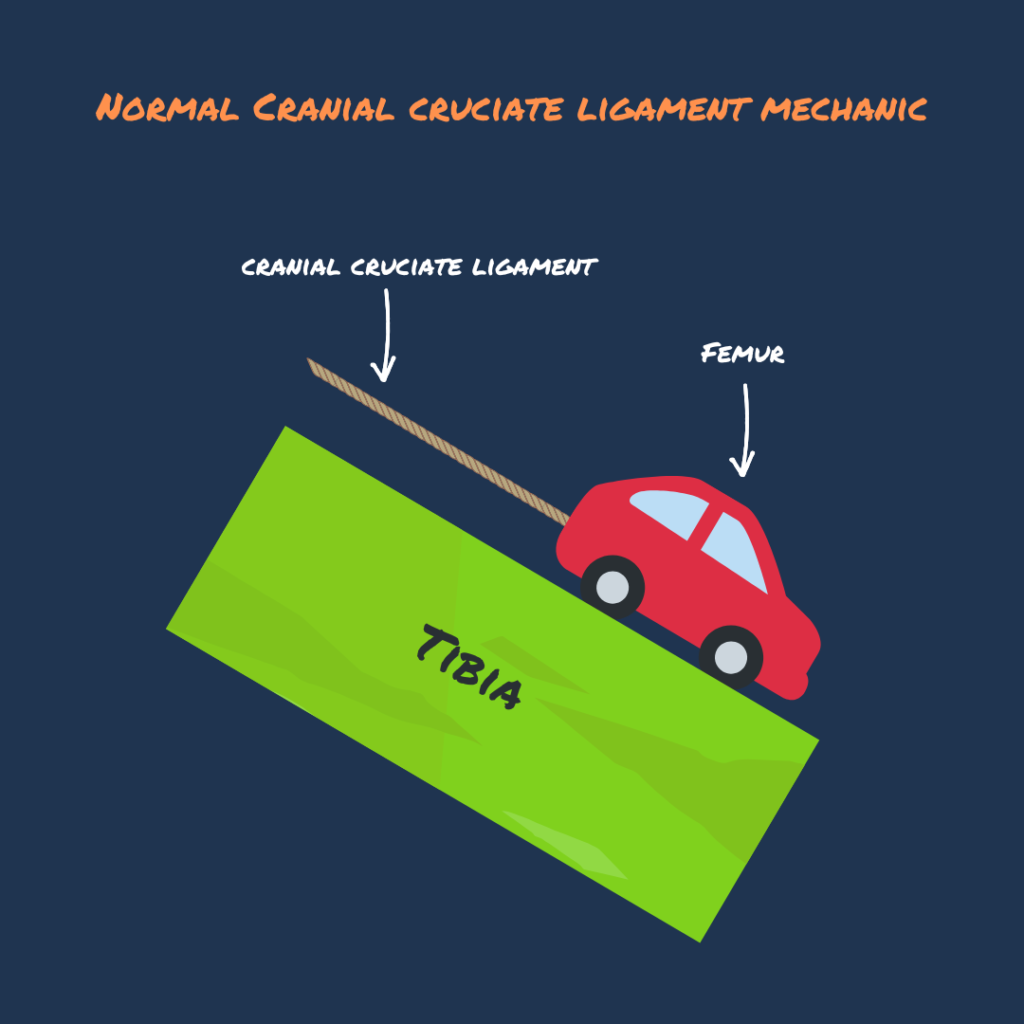

Pic 2 (Rupture ligament): When the rope (cranial cruciate ligament) breaks, the red car🚗 (Femur) will continuously slide down the slope ⛰ (Tibia), resulting in pain.